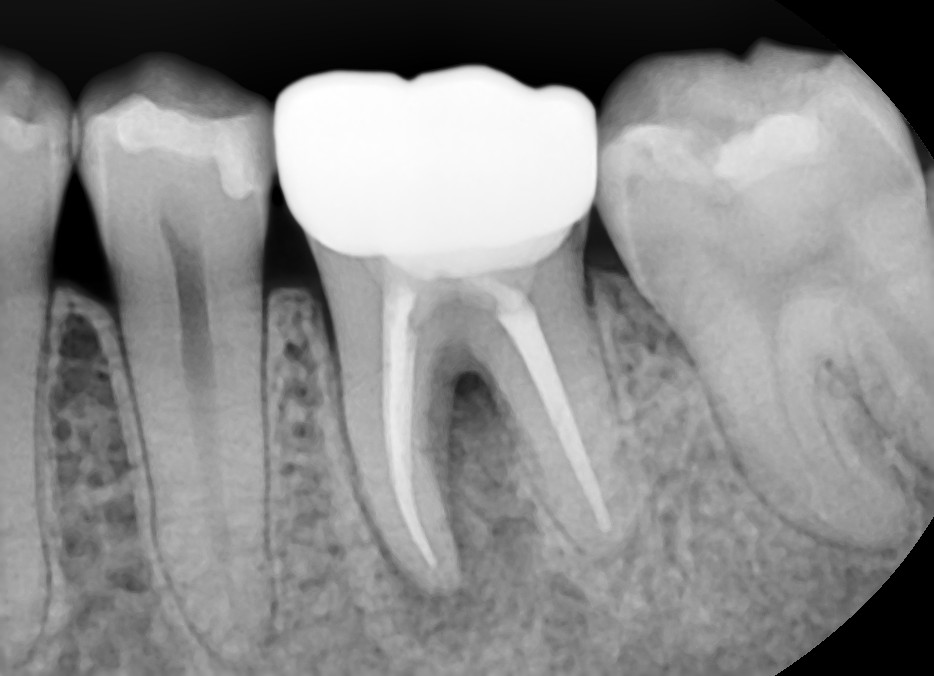

Case #2

치료 전